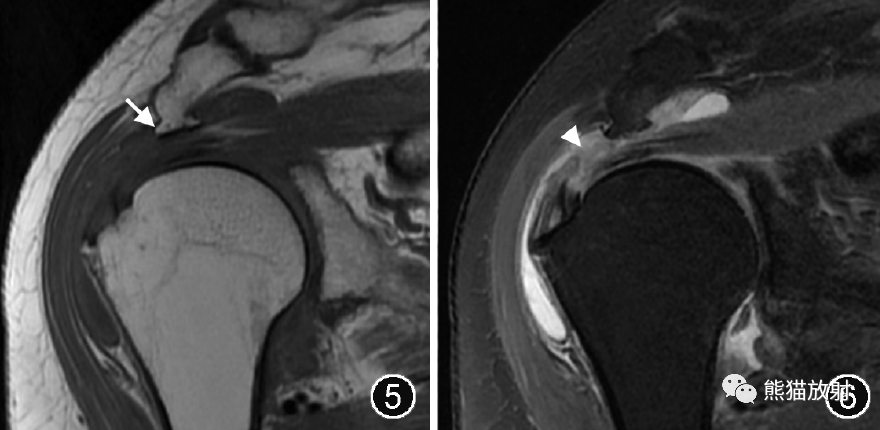

喙肩韧带增厚、钙化在斜矢状面上显示最佳,其肩峰附着处可有骨刺形成,尖端指向喙突(图7, 8, 9)。

图8,9 喙肩韧带附着处骨刺伴肩峰下撞击综合征的MR图像。肩关节MR平扫斜矢状面T1WI(图8)示喙肩韧带肩峰附着处骨刺形成(↑),肩峰下间隙狭窄,斜冠状面脂肪抑制T2WI(图9)示冈上肌腱信号增高、滑囊面纤维不连续(↑),肩峰下-三角肌下滑囊积液、滑膜增生